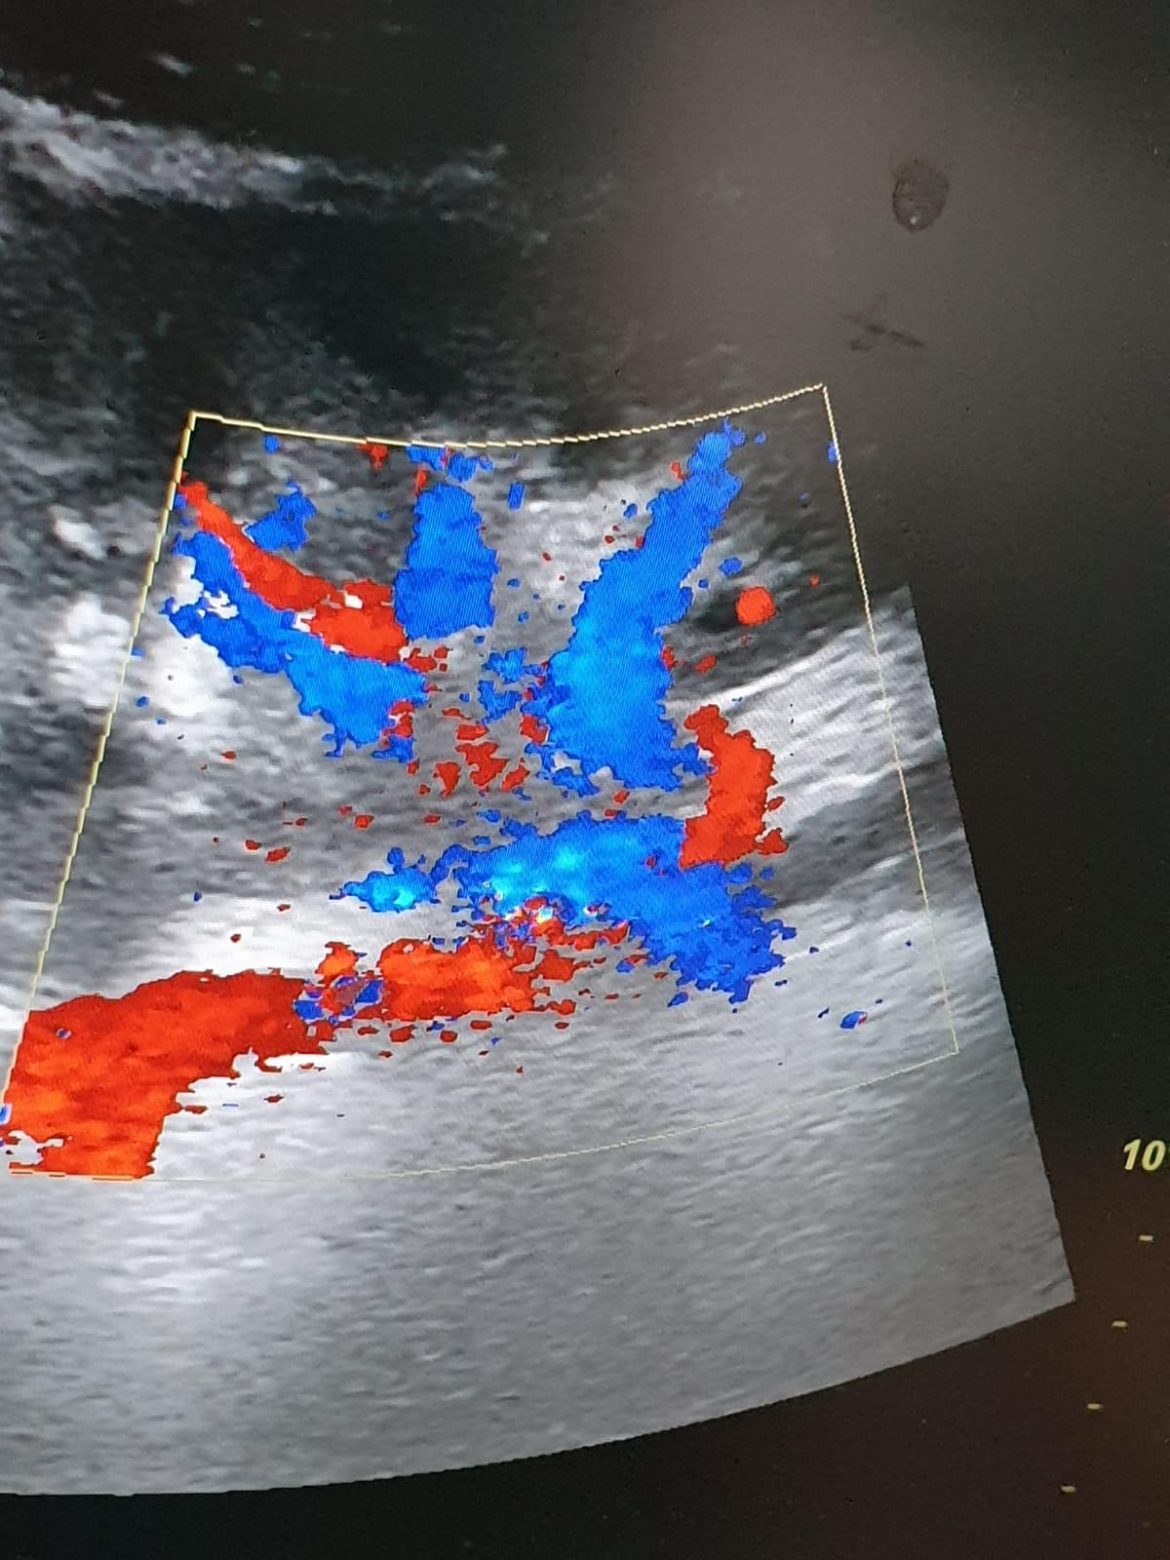

Transplantul este una dintre cele mai complicate intervenții chirurgicale, iar dacă pacientul prezintă și o stare de sănătate precară, riscurile sunt enorme. Din cauza unor depuneri de calcar pe vasele de sange, un pacient pe dializă a așteptat 7 ani să poată primi un rinichi. În ciuda complicațiilor, medicii de la CLuj au reușit să efectueze operația cu ajutorul unei tehnici noi, învățate în Turcia. Ce presupune aceasta și cum se simte pacientul aflați dintr-o nouă ediție Agenda Look.